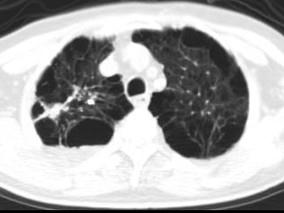

问题 男,76岁,气喘数年,胸痛一月余,结合影像图像,选择最可能的诊断 ( )

选项 A、右上肺错构瘤 B、右上肺肉瘤 C、肺间质纤维化 D、右上肺瘢痕癌 E、右上肺结核球

答案 D